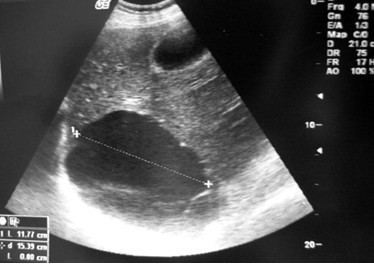

1、7W+1D的BC数据 胎囊2.91.9 生的是男孩

2、9W+4D的BC数据: 宫内见46.630.2mm孕囊 双胞胎都是女孩

3、60天的BC数据: 孕囊大小是3.61.6MM 生下的是帅哥

4、5W+6D。孕囊:25mm11mm 男孩

5、数据:胚囊:23×17×16 生下的是小美女

6、46天BC数据孕囊:201717 女孩

7、7w+1D的BC结果:3220mm妊娠囊 女孩

8、8周时是1.6×1.7 生下的是千金

9、8周的时候是4128MM 生下的也是女宝宝

准妈妈们学会了吗?快拿出B超单来看看自己的小宝宝是男是女吧,不过要是把这疑问留到最后,等到宝宝出生的一刻,是不是也很有惊喜。